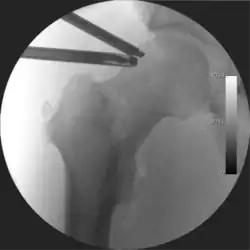

Figure 4. A needle is passed into the joint, breaking the 'suction seal', and allowing further distraction of the hip joint with minimal extra traction -

The next step is to insert a fine needle under x-ray guidance into the hip joint. This breaks the 'suction seal' of the joint and allows further distraction if necessary (see fig 4). The surgeon wishes to see the ball move out the socket by approximately 1 cm, so that access to the hip joint can be achieved with minimal risk of damage to the joint surfaces. Most surgeons will inject fluid into the joint at this stage, again to ensure that there is enough space between the ball and socket for safe instrument access. This needle is then removed. The next step is placement of the 'portals', or the small holes made to pass instruments into the joint. This is achieved by again passing a fresh hollow needle into the joint under x-ray control, usually in a slightly different position. The reason for this is so the surgeon can ensure that the needle, and subsequent cannulae do not penetrate and damage the acetabular labrum or cartilage joint surfaces (see fig. 5). Again, surgeons will have their own preferences as to their preferred placement. Through this hollow needle, a long thin flexible guide wire is passed into the joint, and the needle is removed over it, leaving the guide wire in situ. A small cut in the skin is made around the wire, to allow for larger cannulae to be placed over the wire through the portal. The wire therefore guides the larger cannulae into the joint. The most common external diameters of cannulae used are between 4.5 and 5.5 mm. Once the surgeon is satisfied that the cannula is in the correct position, by a combination of feel and x-ray guidance, the guide wire can be withdrawn. Once the first portal is correctly placed, any further portals may be created once the camera is in position, to ensure that they are placed with minimal risk to the joint surfaces. This process can be repeated to gain as many points of entry to the hip joint as the surgeon requires, normally between two and four. Certain of these entry points will be used for the viewing arthroscope and others for operating instruments.